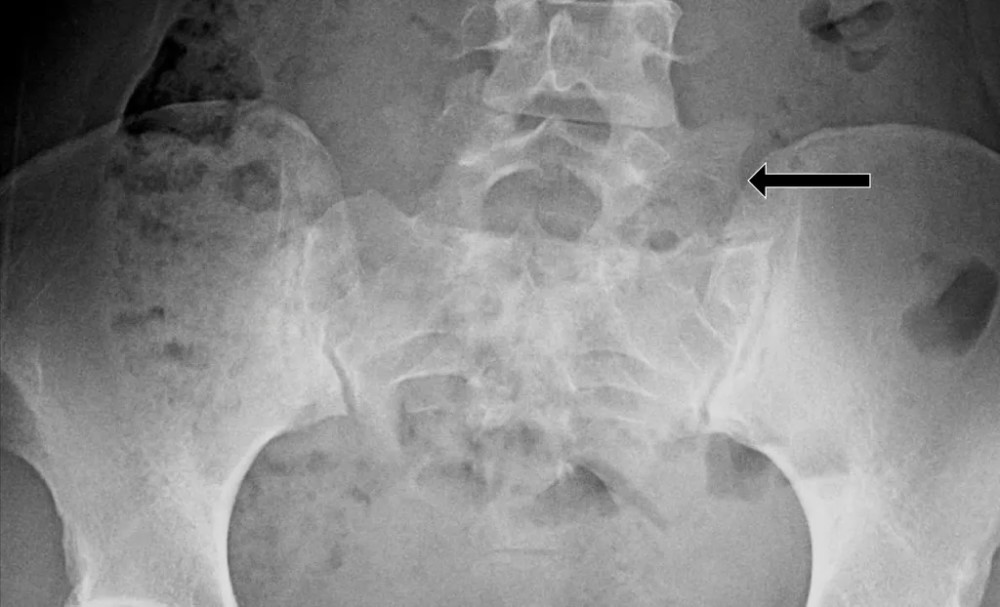

文章插图

腰椎 X 线片示:L5 左侧横突肥大 , 间隙变窄 , 假关节形成 , 为 Ⅱa 型

黑色箭头所指处